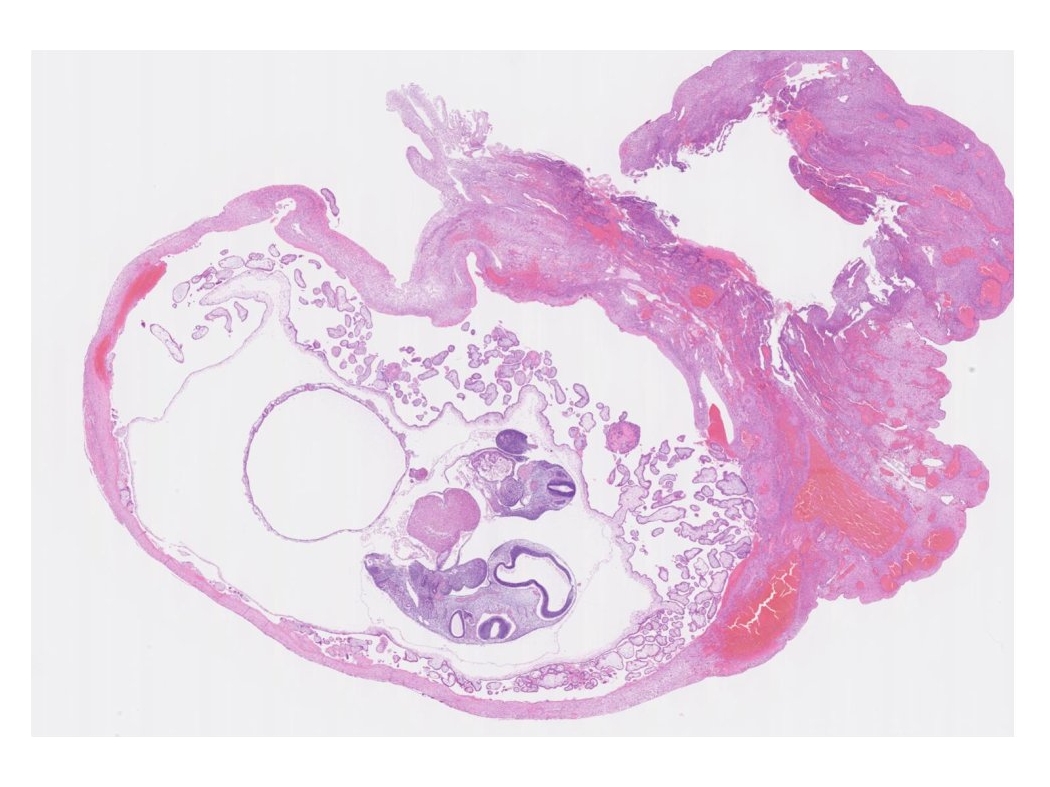

Gestational Sac

妊娠推定5-6週でAbortion

羊膜と絨毛膜との間の絨毛膜腔に卵黄嚢yolk sac が見られる。絨毛膜には絨毛に富む有毛部と反対側の無毛部(絨毛は消失する)がある。